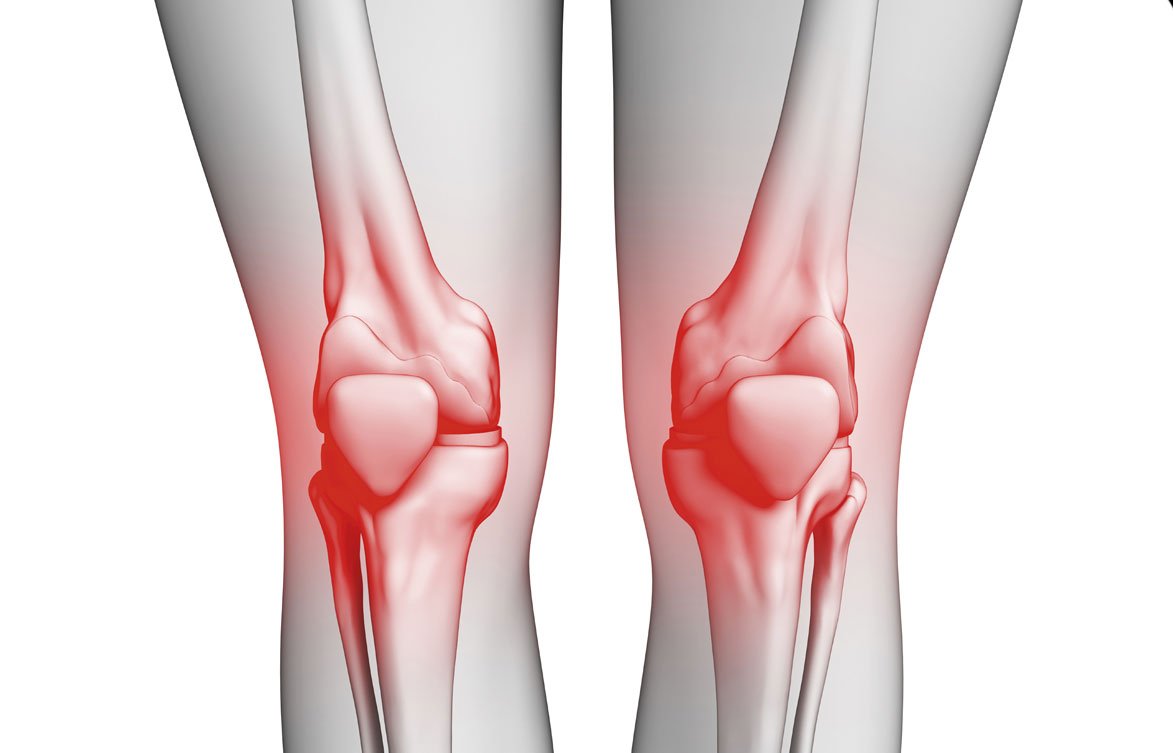

2. علاج ألم المفاصل والركبة:

أنواع آلام المفاصل وأسبابها

آلام المفاصل هي مشكلة صحية شائعة تؤثر على العديد من الأشخاص في مراحل مختلفة من حياتهم. تختلف أسباب وآلام المفاصل حسب نوع المرض أو الحالة التي يعاني منها الشخص. فيما يلي أبرز أنواع آلام المفاصل وأسبابها:

التهاب المفاصل التنكسي (الفصال العظمي)

- الوصف: هو أكثر أنواع التهاب المفاصل شيوعًا، ويحدث عندما يتآكل الغضروف الذي يغطي المفصل، مما يؤدي إلى احتكاك العظام ببعضها البعض.

- الأسباب: تقدم العمر، إصابات سابقة، العوامل الوراثية، زيادة الوزن، الاستخدام المفرط للمفصل.

آلام المفاصل بسبب زيادة الوزن

- الوصف: زيادة الوزن تؤدي إلى تحميل ضغط إضافي على المفاصل، خاصة مفاصل الركبتين والوركين.

- الأسباب: السمنة وزيادة الوزن تؤدي إلى إجهاد المفاصل وتسبب آلامًا على المدى الطويل.

كيفية علاج آلام المفاصل

- التردد الحراري: يعتبر من أفضل العلاجات الحديثة التي تستخدم في تخفيف آلام المفاصل، حيث يتم تطبيق موجات تردد حراري عالية لتحفيز الأنسجة والعصب المحيط بالمفصل، مما يساعد في تقليل الالتهابات وتحسين حركة المفصل. هذا العلاج يُستخدم بشكل شائع لعلاج آلام المفاصل المزمنة والألم الناتج عن التهاب المفاصل.